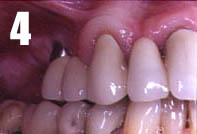

In the case presented, with treatment of a maxilla, a fixture is placed in front of the sinusí frontal border. By angling the fixture posteriorly, it is possible to fit a long fixture which opens in the region of the second premolar (Fig. 1). After 6 months healing, the abutment connection can be made. In this case, a 32° angulated abutment is used.

After preparing and laying open the supporting teeth, in this case nos. 13 and 11, the abutment is provided with an impression coping (Fig. 2). An impression is taken with an elastomer. The bridge is made of porcelain fused to metal with an intracoronal attachment, in this case McCollum, and with a palatinally placed horizontal locking screw which prevent vertical gliding (Fig. 3). The construction allows the implant-supported portion of the bridge to be taken off when necessary, e.g. when tightening the abutment screw. The bridge is cemented in the usual manner on the supporting teeth with simultaneous tightening of the gold screw in the implant-supported section. The bridge is cemented (Fig. 4), smile! (Fig. 5).